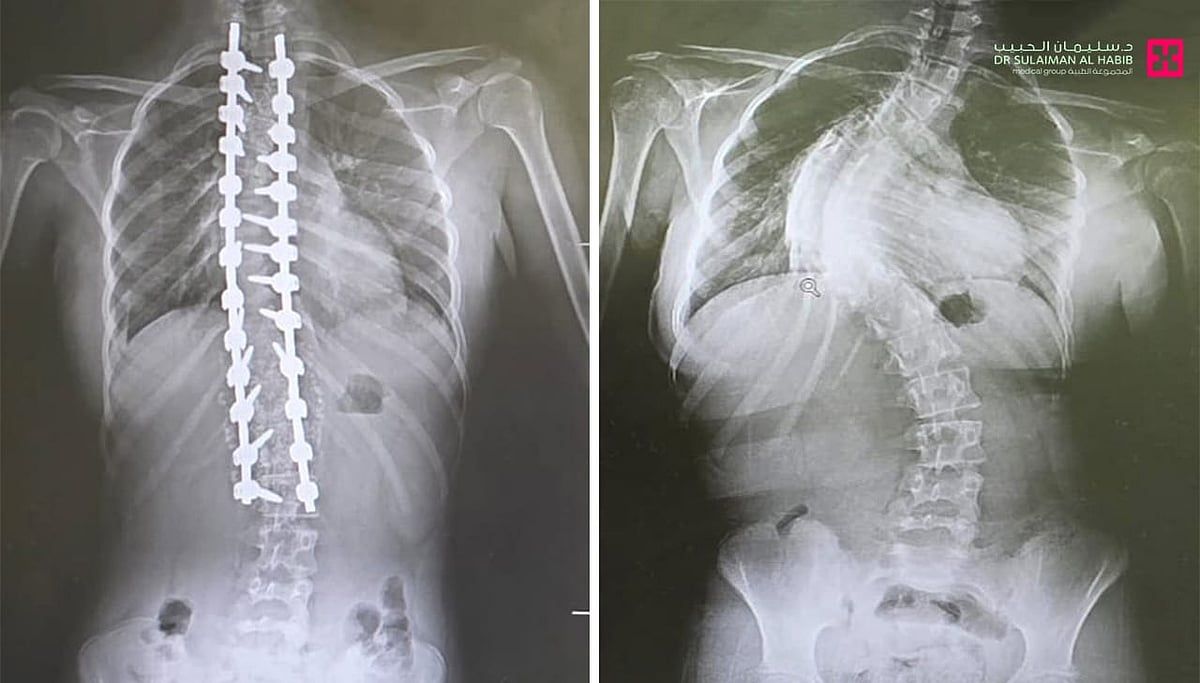

حيث جاءت المراجعة إلى المستشفى وهي تشتكي من تحدب وإنحاء جانبي، وآلام حادة ومزمنة في الظهر، وغيرها من الأعراض التي تسببت مجتمعة في الحد من حركتها، وقدرتها على ممارستها حياتها بشكل طبيعي، وعقب وصولها إلى المستشفى تم إخضاعها للفحوصات المخبرية وأشعة الرنين المغناطيسي Mri والأشعة السينية X- ray لكامل منطقة الظهر، حيث أكدت النتائج وجود انحراف مزدوج وحاد بزاوية "95" درجة، وأخضعها الفريق الطبي لعملية جراحية، تم فيها تقويم العمود الفقري باستخدام البراغي والقضبان المعدنية، وتثبيت ودمج الفقرات، واستخدمت في العملية، مجموعة من أحدث الأجهزة الطبية منها الجراحة الملاحية Spinal Navigation Surgery، الميكروسكوب Pantero ومراقبة الأعصاب electrophysiology والتي ساهمت في إنجاح التدخل الطبي.

وحولت المراجعة بمؤشرات حيوية مستقرة إلى العناية المركزة ووضعت تحت المراقبة لمدة "24" ساعة ومن ثم نقلت إلى غرفة التنويم وتحسنت حالتها من العناية الطبية الحثيثة، حيث تمكنت من المشي بعد "24" ساعة من العملية تحت إشراف اختصاصي العلاج الطبيعي، ومن ثم غادرت إلى منزلها بحالة صحية ونفسية ممتازة بعد "5" أيام من العملية، وأكدت فحوصات ما بعد العملية أن الميلان تم تعديله بنسبة تفوق الـ"98%" مع الحفاظ على سلامة الأعصاب، إضافة إلى أنها استعادت القدرة على الحركة والمشي بتوازن، والاستلقاء والنوم على ظهرها، فضلاً عن القوام والمظهر الطبيعي، بعد تعديل وضعية الحوض والكتف، كما أن طولها مع النجاح الكبير للتعديل زاد.